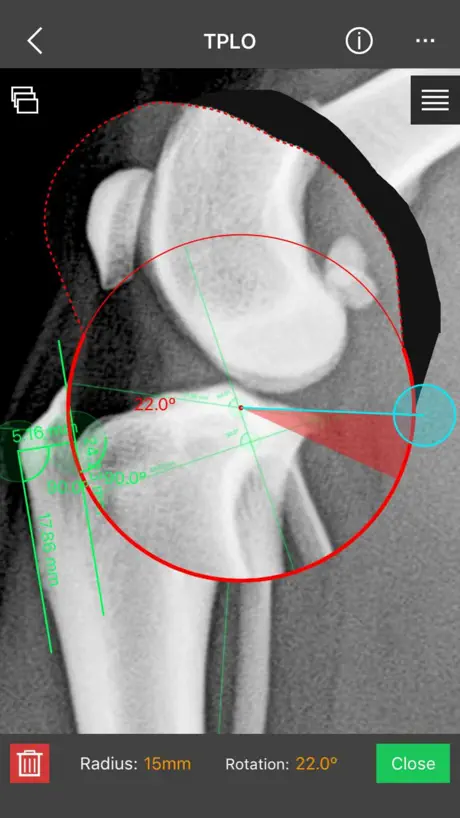

This is a useful tool for traumatology and orthopaedic surgical planning veterinary, including advanced techniques for treat canine anterior cruciate ligament (ACL) injuries (TPLO and CTWO).

f) Circular cut, TPLO.

m) TPLO plates

This is a useful tool for traumatology and orthopaedic surgical planning veterinary, including advanced techniques for treat canine anterior cruciate ligament (ACL) injuries (TPLO and CTWO).

f) Circular cut, TPLO.

m) TPLO plates